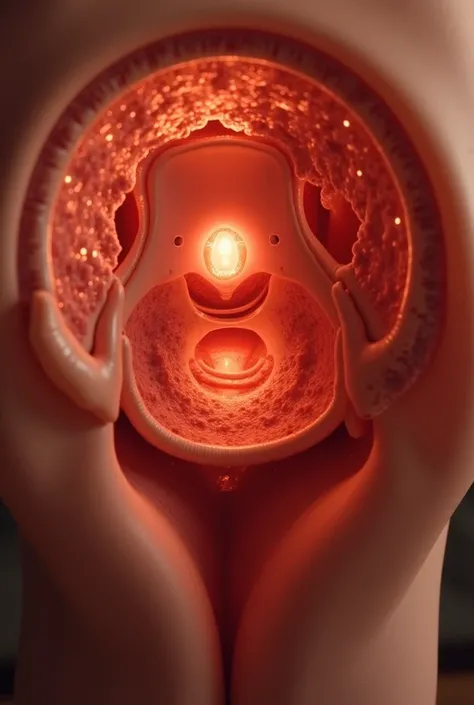

Image of a 10-week-old embryo in a uterus, captura, maternal photography 4 k

Image of a 10-week-old embryo in a uterus, captura, maternal photography 4 k, high quality scan, extremely high quality scan, high resolution scan,, video still, feto, webcam footage, high resolution scan, Escaneo profesional de alta calidad, metraje realista. hiper realista

Image of a 10-week-old embryo in a uterus

feto